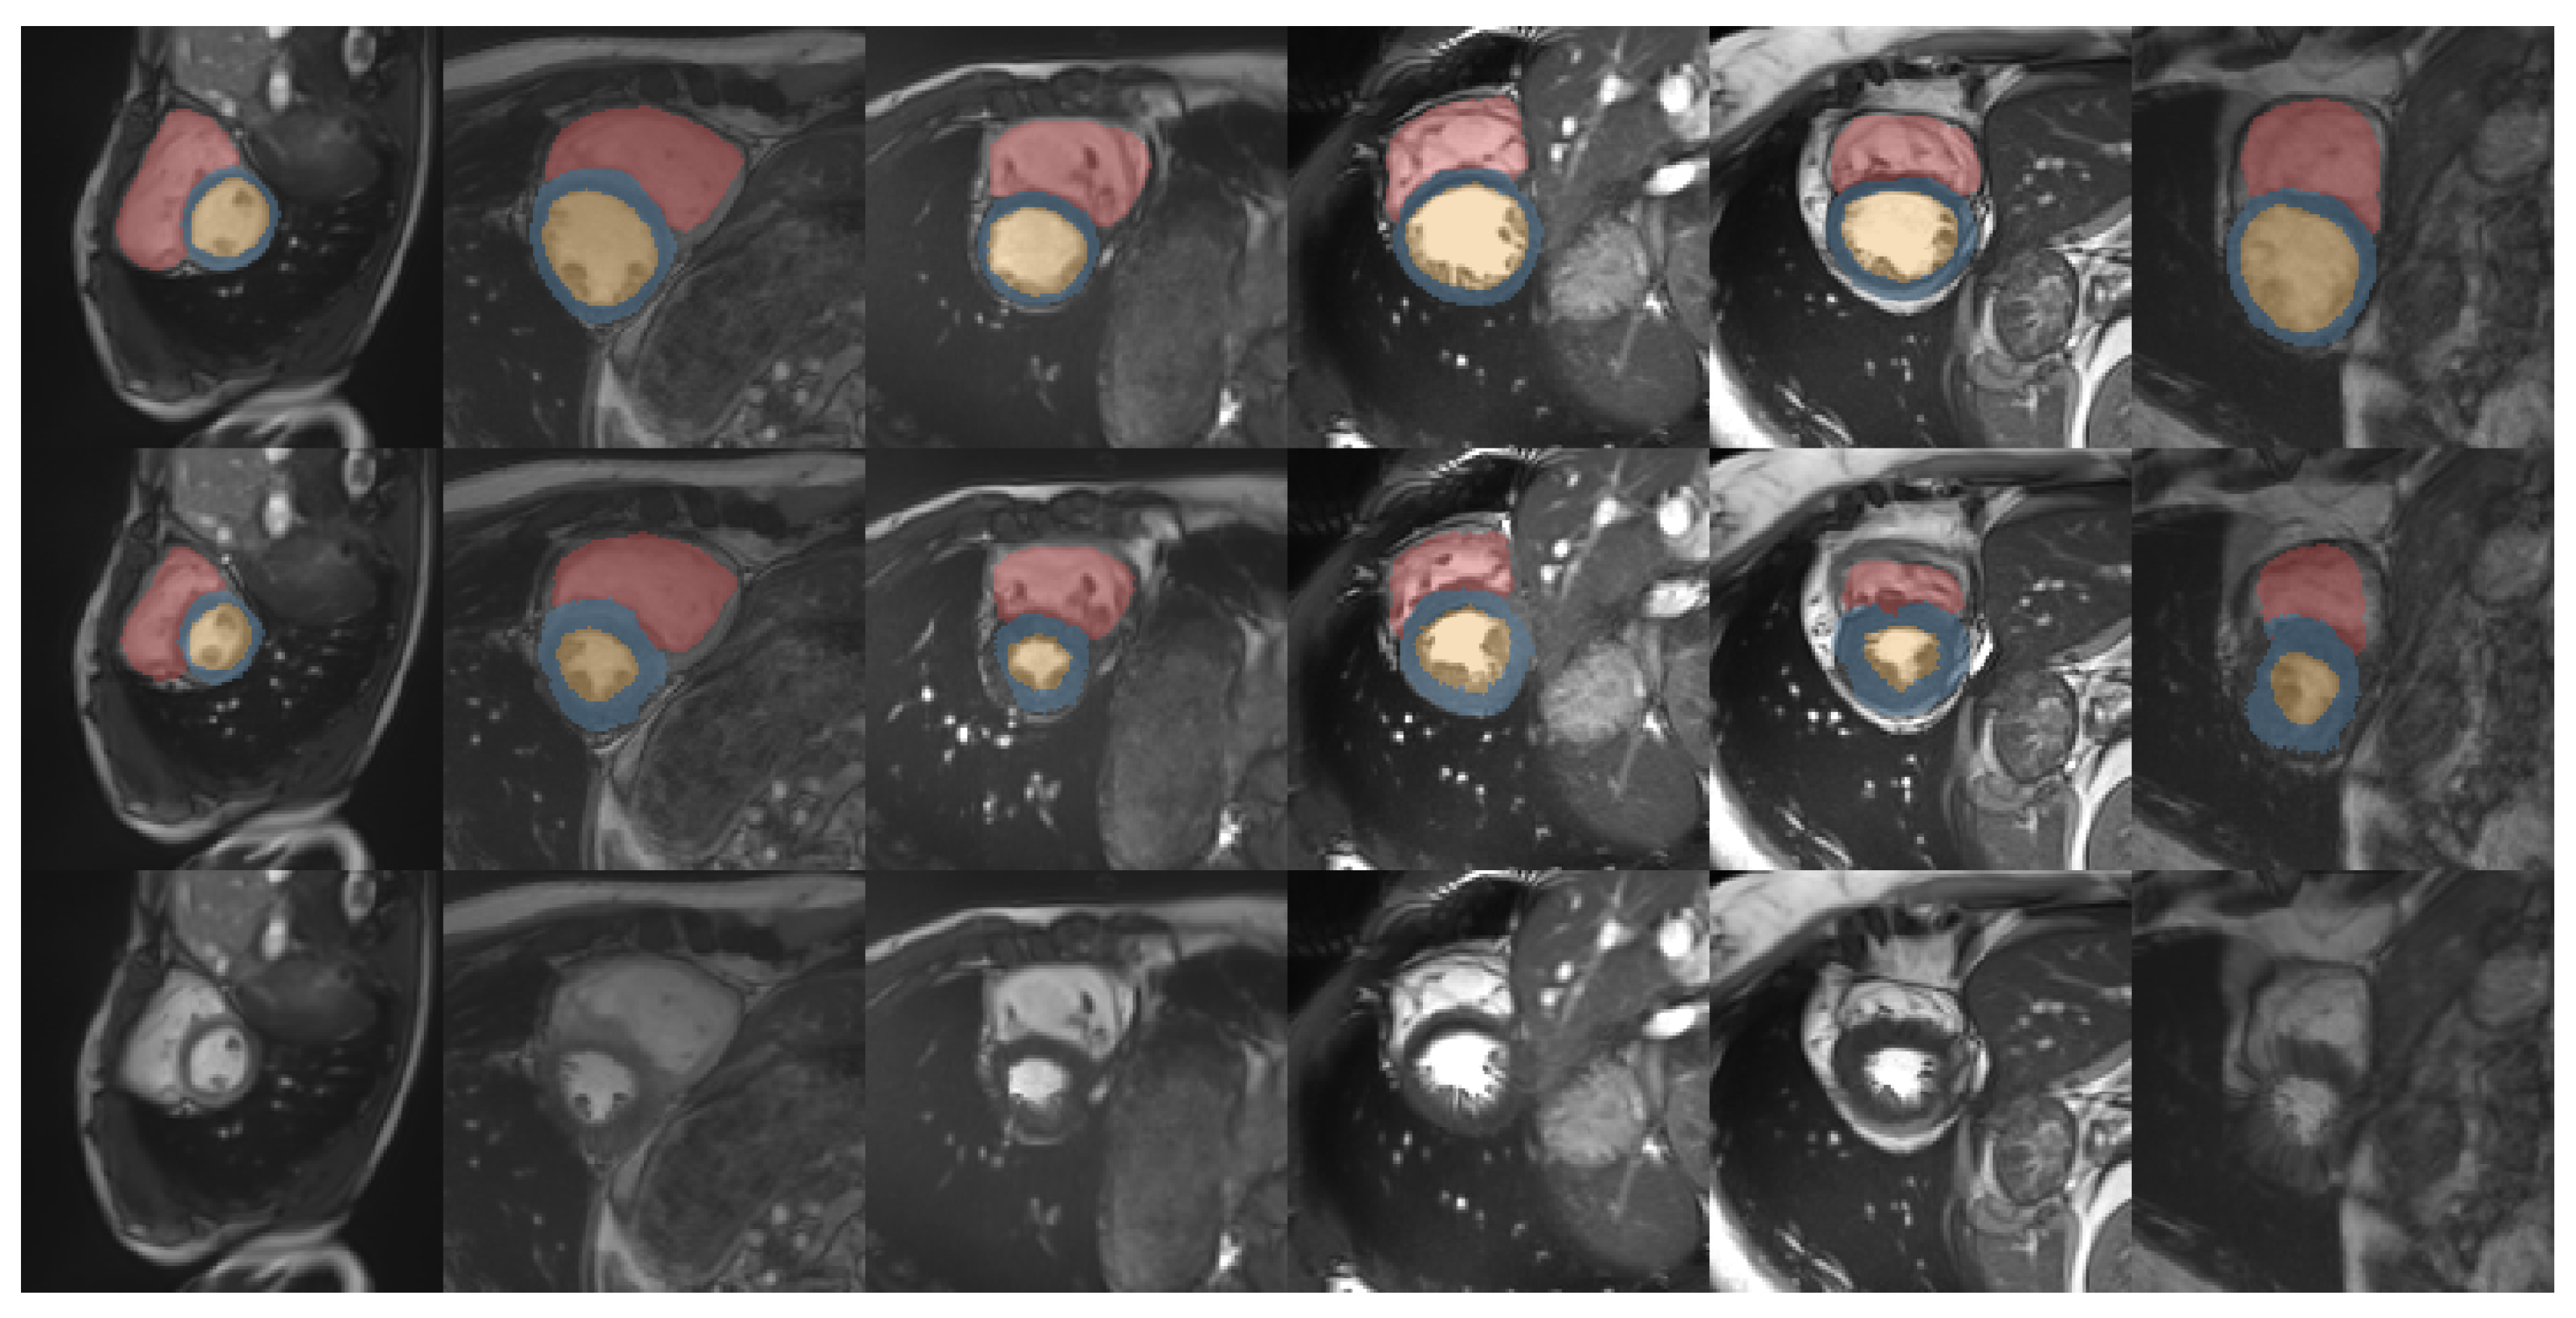

3.3. Medical Cardiac Image Registration

| Unregistered | LCC-Demons [26] | Voxel-Morph [24] | Krebs et al. [25] | Ours | |

|---|---|---|---|---|---|

| R.V. | 65.1 | 70.6 | 68.1 | 68.4 | 77.4 |

| L.V. | 66.0 | 77.6 | 74.3 | 75.6 | 82.5 |

| Myocard | 52.5 | 73.0 | 69.7 | 70.4 | 73.4 |

| Mean | 61.2 | 73.7 | 70.7 | 71.5 | 77.8 |